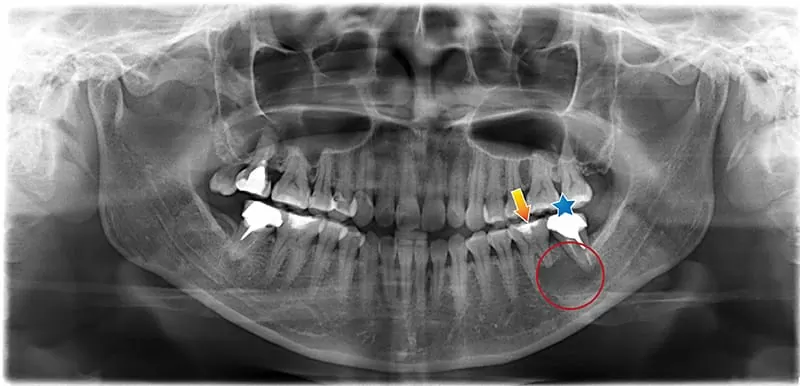

術前 全口X光片

患者因想改善齒列及外觀來院評估,在全口健檢的過程中發現:

- 左下臼齒區域 (圈選處) 出現巨大病灶且造成左下第一大臼齒 (箭頭處) 牙根吸收,牙髓神經部分壞死。

- 左下第二大臼齒(星星處)舊有根管治療未達理想,也受病灶侵犯。

因此決定配合顯微鏡的使用進行左下第一大臼齒(箭頭處) 根管治療,及左下第二大臼齒(星星處) 重新根管治療,以期病灶縮小後,再進行手術摘除病灶。